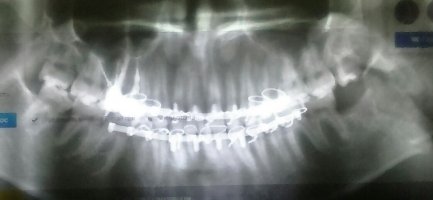

Мой муж неделю назад сломал челюсть, после шинирования кость до сих пор немного движется и когда он через трубочку кушает, то языком чувствует кость торчащую (перелом открытый).

Нас интересует вопрос: как скоро кость «схватится» и чем чревато то, что она торчит вовнутрь? Также температура не спадает (37,0-37,2), из-за чего это?